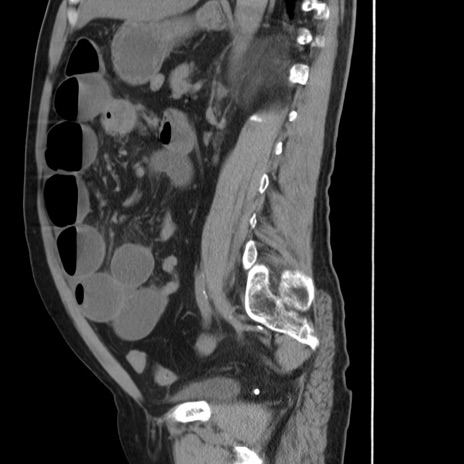

症例20(矢状断像)

【症例】 60歳代男性

【主訴】 腹部膨満、嘔吐

【現病歴】5日前頃より倦怠感を認め食事量減少し4日前の朝嘔吐、食事摂取困難となった。 3日前近医受診し点滴施行され整腸剤などを処方された。 当日他院を受診し、腹部膨満著明、炎症反応の上昇(CRP10.8、WBC11200)あり、紹介受診となる。

【身体所見】 意識JCS1 受け答えがはっきりしないBP 111/57mHg、 P 67bpm、、BT35.2°C、SpO2 97%(RA)、 腹部:膨隆、打診で鼓音あり、全体的に圧痛有り、腸蠕動音(-)、反跳痛ははっきりせず。

【データ】WBC 11400、CRP 14.20